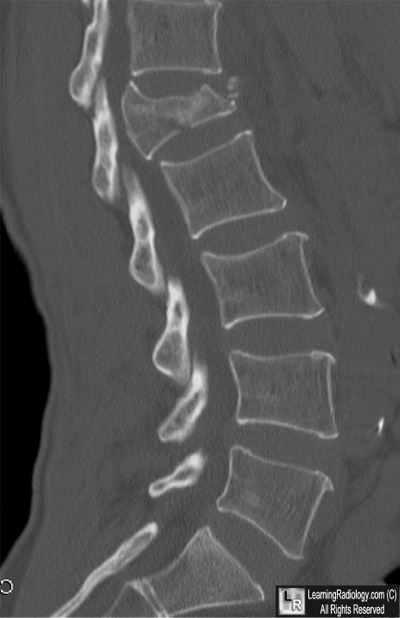

Sagittal CT Reconstruction of Lumbar Spine

5. Burst Fracture

Burst Fracture

- Burst fractures result from axial loading most often secondary to motor vehicle accidents and falls

- The axial load drives the intervertebral disk into vertebral body below

- Usually produces a comminuted, vertical fracture through the vertebral body

- Fragments may be retropulsed into the spinal canal injuring the cord